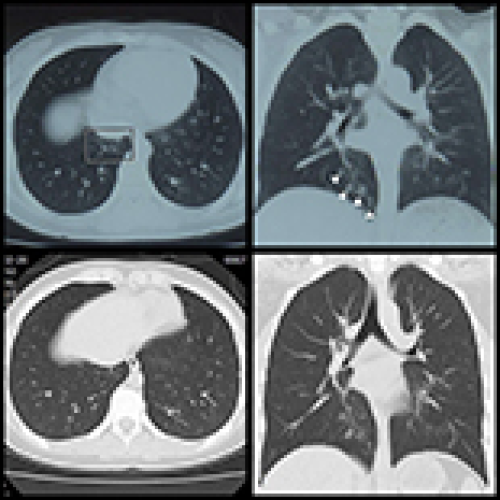

14 Nov 2021 : Clinical Research

Clinical Features and Temporal Lung Radiographic Changes in 25 Patients Recovering from COVID-19 Pneumonia: A Retrospective Case-Control Study

Chao Hu, Jian Ping Zeng, Ke Peng, Hong Xia, Huan Ming Zhang, Zhi Zhong, Ming Yan Jiang

DOI: 10.12659/MSM.933381

Med Sci Monit 2021; 27:e933381

3,640 973 0

3640 973 0